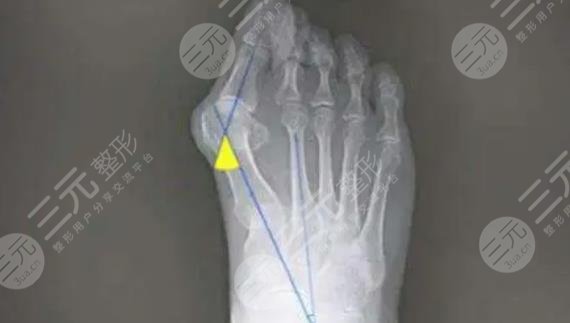

緩解大腳骨外翻的方式比較多,具體選擇哪一種方法需要根據(jù)每個(gè)人的病情去評估。在選擇方式之前,要根據(jù)患者的癥狀,通過身體的檢查和X線來綜合去判斷,不可以盲目的去選擇,因此一定要到正規(guī)的醫(yī)院,請經(jīng)驗(yàn)豐富的醫(yī)生去幫助選擇和緩解。在緩解之后也要定期進(jìn)行康復(fù)訓(xùn)練,避免一些不良反應(yīng)出現(xiàn)。